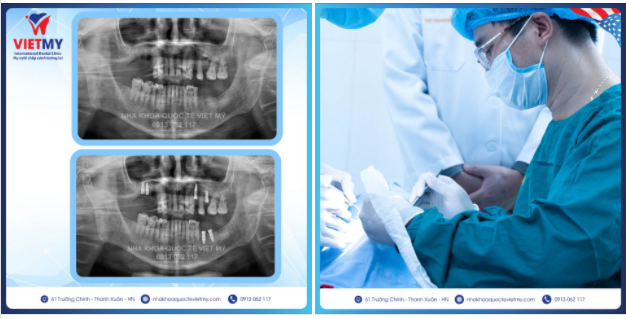

Mất 3 răng liền nhau cấy 2 trụ Implant được không